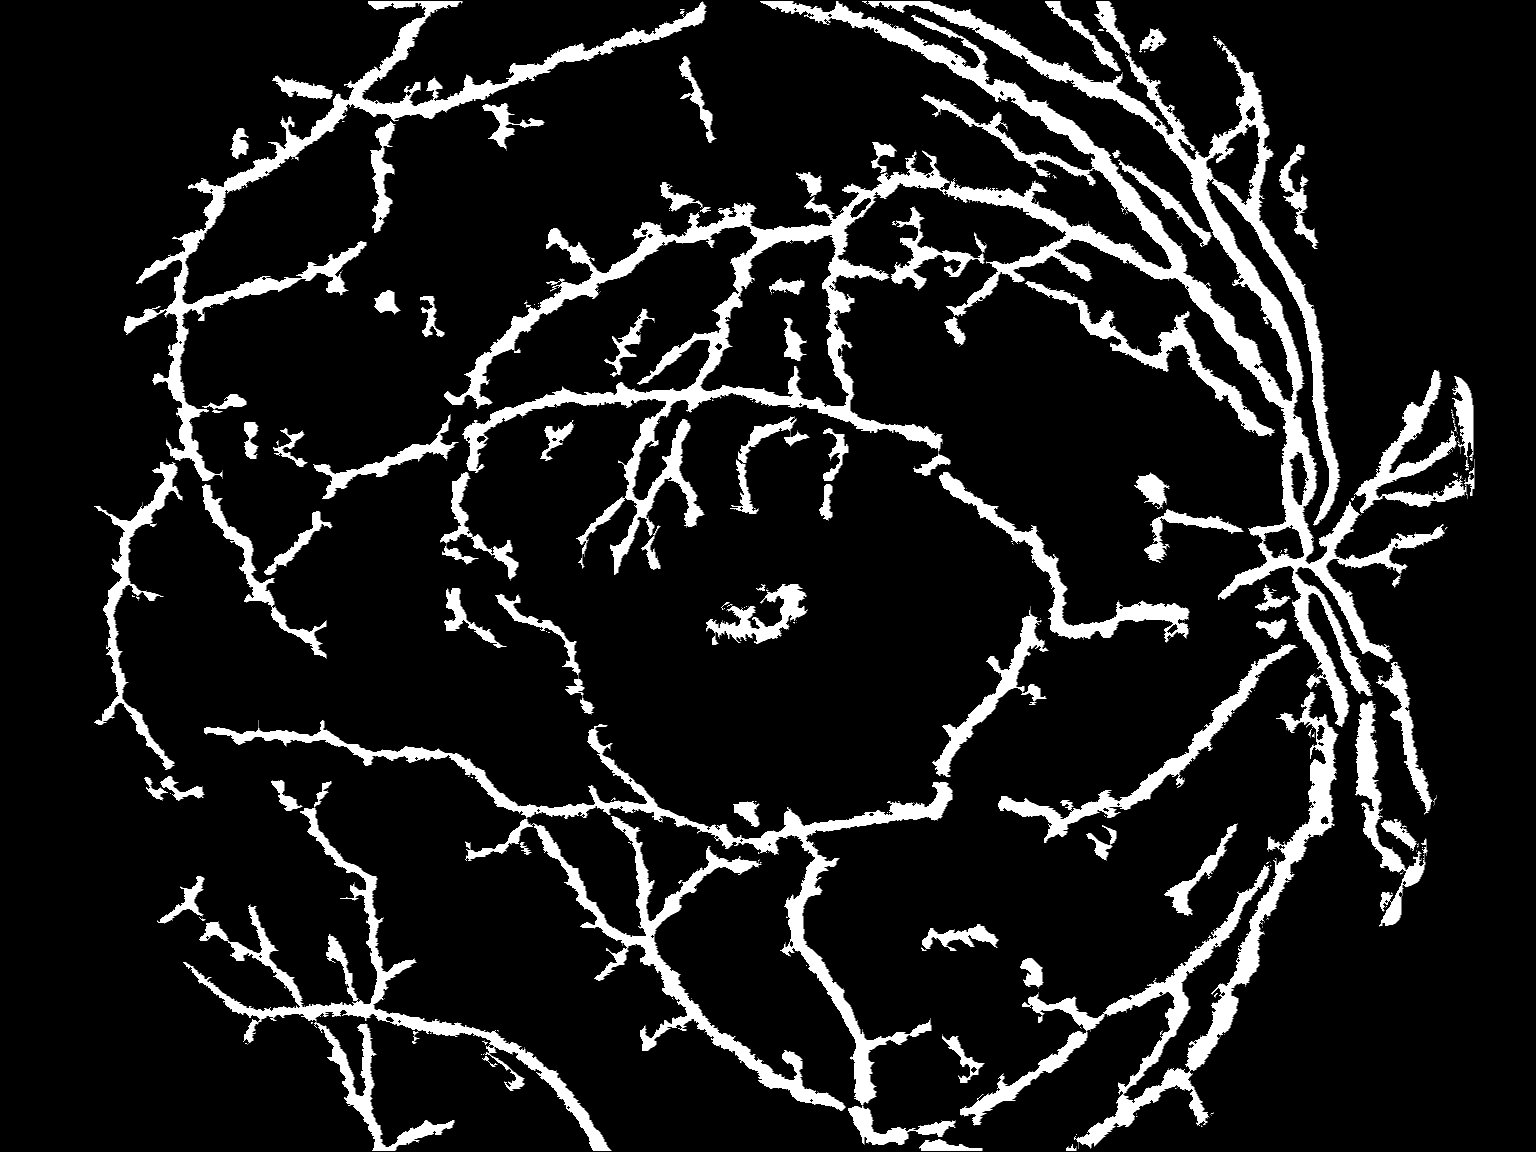

Hi阈值图像

筹备和清理:

current = np.copy(thresh_hi)

prev = np.copy(current)

prev[:] = 0

current = cv2.morphologyEx(current, cv2.MORPH_OPEN, kernel5)

初始掩模

去除小气泡后

结果